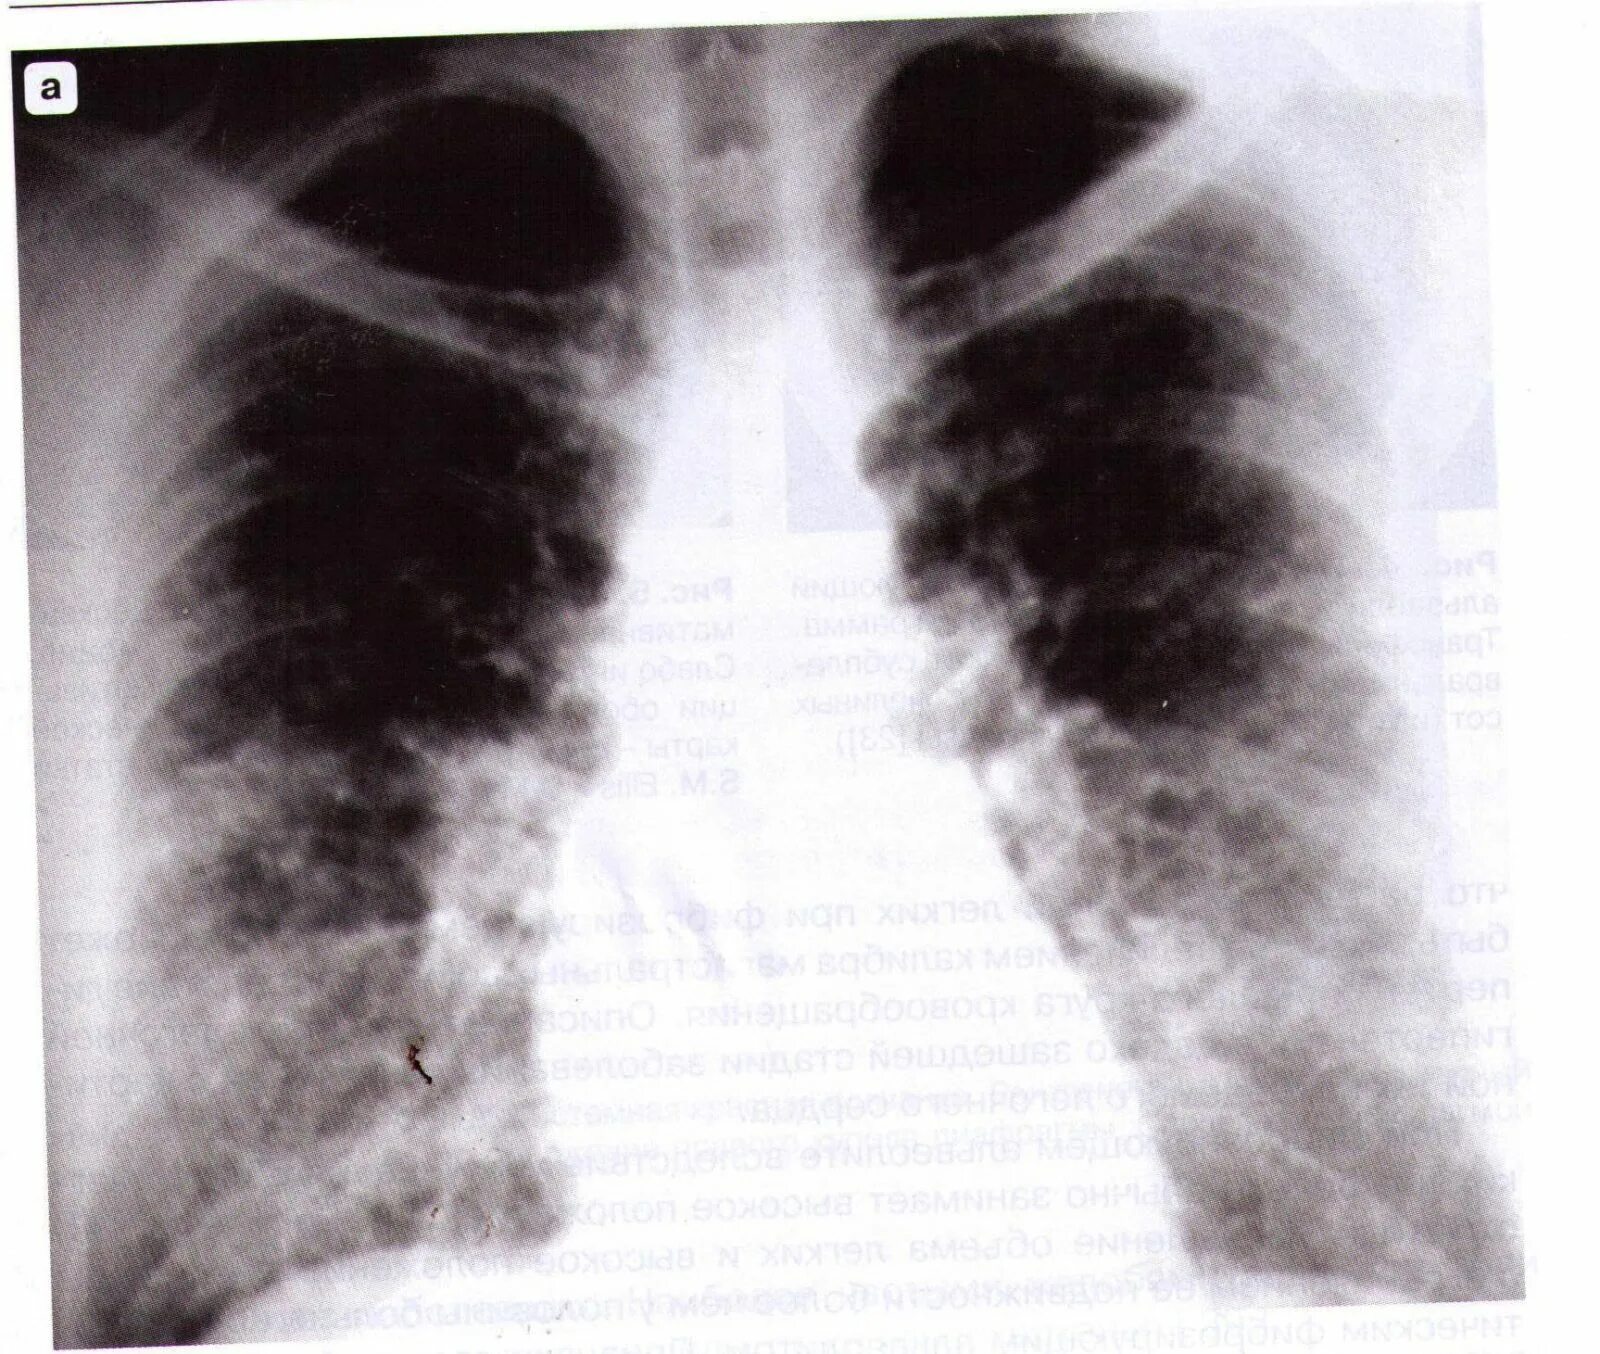

Пневмосклероз рентгенограмма